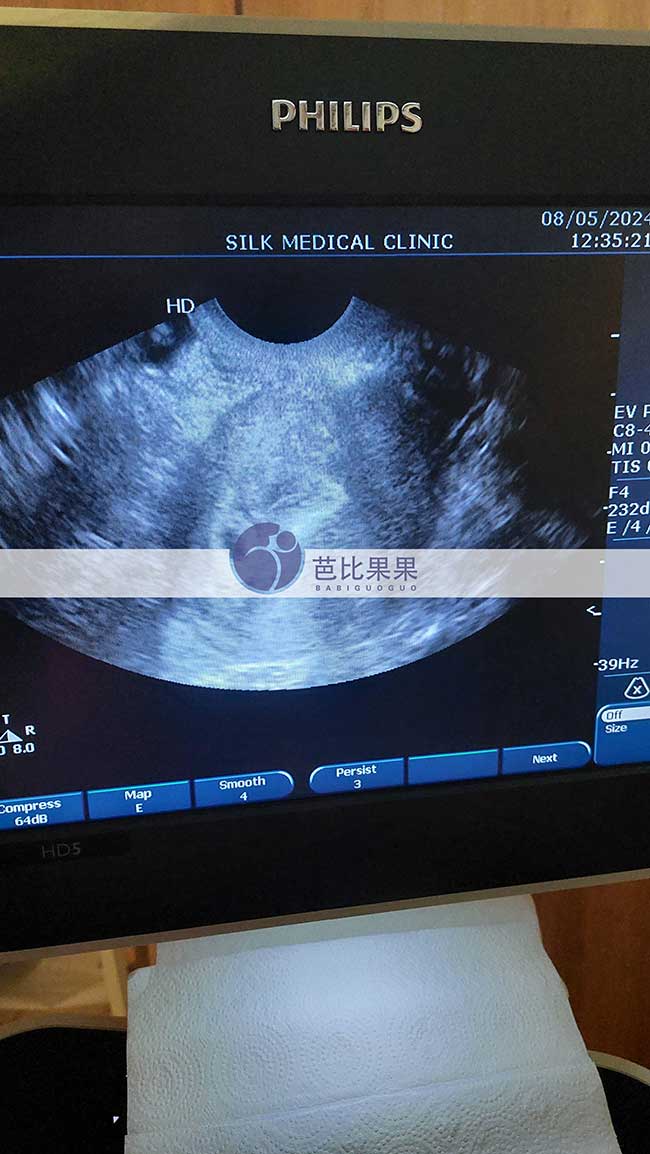

S女士在格鲁吉亚补偿的哈萨克斯坦试管妈妈来做第一次B超

深圳S女士在格鲁吉亚补偿的哈萨克斯坦试管妈妈来做第一次B超啦,看到了孕囊宝宝,等待两周后第二次B超